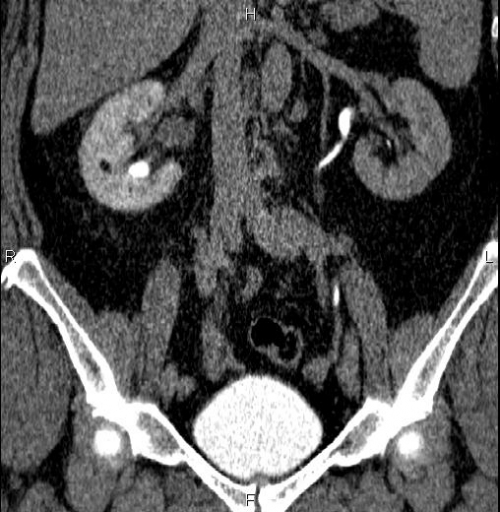

Изображения КТ конкрементов мочевого пузыря